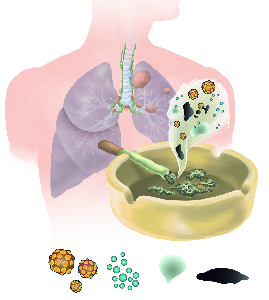

Detailreiche Fotografien aus der medizinischen Praxis ergänzen die Texte; moderne, genaue,

wissenschaftliche Zeichnungen geben Einblick in die Anatomie und die Funktion der Lunge und

anderer Organe.